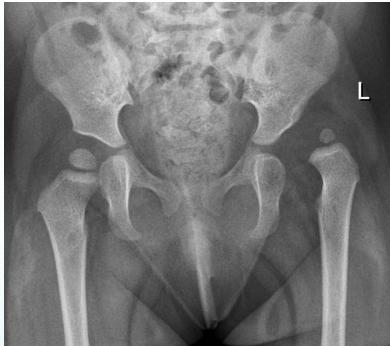

Radiographic Stages:

-

Initial/ Bone Death Stage (Sclerosis)

- May initially appear normal on x-ray

- Increased density followed by collapse

Revascularization and Repair Stage

- Reduced density and fragmentation on x-ray

Distortion and Remodeling Stage

- Distortion, flattening (coxa plana)

- Enlargement (coxa magna) with partial uncoverage

Radiological Progression:

Progression: Sclerosis → Collapse → Fragmentation → Remodeling

Imaging Examples: